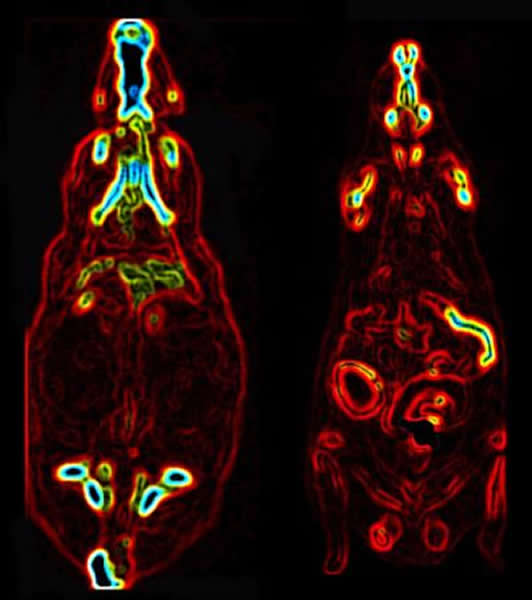

老鼠胃旁路手术前(左)后(右)的PET/ CT扫描